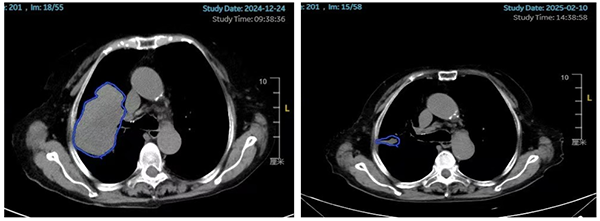

80歲的患者李女士(化名)2024年2月確診為右肺腺鱗癌,經(jīng)過(guò)靶向治療、化療后出現(xiàn)多次進(jìn)展。2024年12月24日查胸部CT提示右肺上葉病灶增大至95mm×64mm(圖1左側(cè)所示)?紤]腫瘤體積巨大,腫瘤內(nèi)部可能出現(xiàn)壞死、乏氧,常規(guī)放療難以取得理想的治療效果,并且大概率會(huì)對(duì)腫瘤周圍的心臟、肺、臂叢神經(jīng)等正常組織造成較大損傷,嚴(yán)重影響患者的生活質(zhì)量,腫瘤放療科副主任丁昕組織蔣愛(ài)軍主任醫(yī)師、李亮副主任物理師等團(tuán)隊(duì)成員進(jìn)行綜合評(píng)估和細(xì)致討論,決定采用空間分割放療技術(shù)。李女士整個(gè)療程接受了6次放療(常規(guī)放療一般至少需要30次),住院時(shí)間明顯縮短。治療結(jié)束后李女士自覺(jué)咳嗽癥狀明顯好轉(zhuǎn),1月后,2025年2月10日復(fù)查胸部CT提示右肺上葉的巨大腫瘤幾乎完全消失(圖1右側(cè)所示),取得了出乎意料的治療效果。

圖1.患者治療前后的影像對(duì)比(藍(lán)色標(biāo)記的為腫瘤部位)